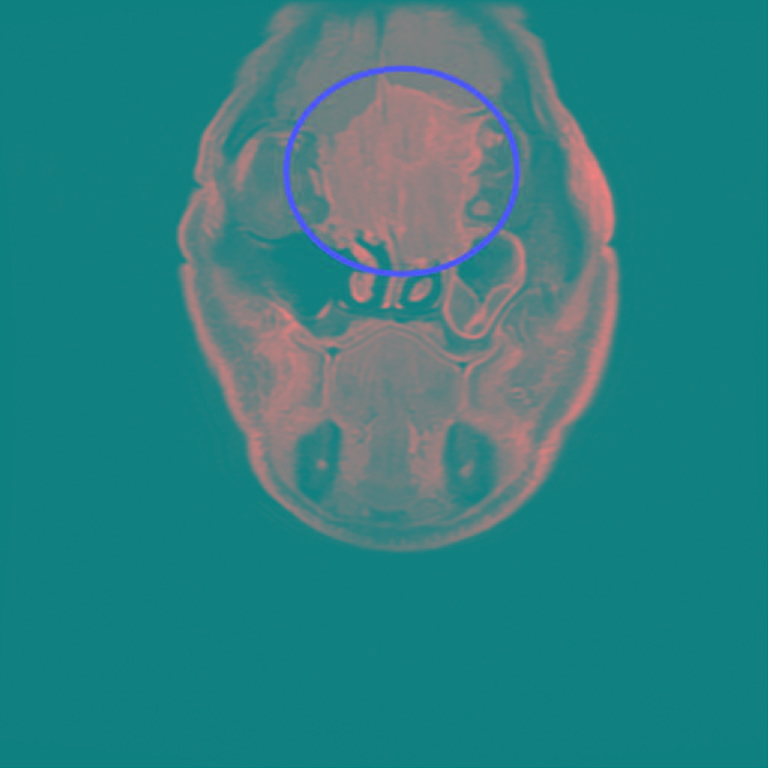

周昱甫副主任表示,第一次看到黃先生時,便發現他眉間額頭微凸、眼距較寬,經過電腦斷層掃描、病理切片檢查,確診腫瘤為罕見的「嗅神經母細胞癌」,且腫瘤已長到6公分,從大腦額葉到雙側眼框到鼻腔上部,佔據整個前顱底並侵蝕到鼻樑骨,雖病人視力未受到影響,但是橫向生長的腫瘤因壓迫到眼外肌,導致病人眼睛無法聚焦,與典型的嗅神經母細胞癌的常見症狀鼻塞、流鼻血等表現症狀大不同。

評估黃先生年紀較大以及病人不願做傳統的開顱大手術,周昱甫副主任以內視鏡顱底手術從鼻孔進入清除腫瘤,不僅傷口小、出血少,減少開顱併發症的風險,且術後3天就能出院。周昱甫醫師說,雖然黃先生是第四期嗅神經母細胞癌,幸運的是未擴散到腦部及眼部,術後治療再以電療及化療消滅殘留在腦膜、眼周膜的癌細胞。